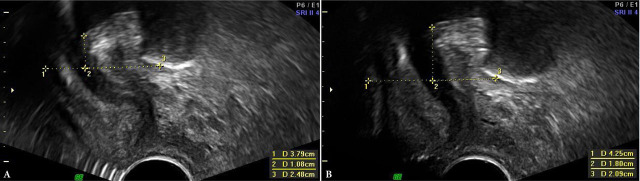

Aim: The aim of the study was to assess the effect of pelvic floor contraction on urethral mobility and the size of the urogenital hiatus, as well as to compare two ultrasonographic approaches for the assessment of urethral mobility: transperineal with a transabdominal probe and transvestibular with a transvaginal transducer.

Materials and methods: Modified Oxford Scale (MOS) was used for clinical evaluation of muscle contraction. The parameters obtained in both ultrasound approaches were assessed for all six Oxford grades. The values of ΔH, ΔD and vector, measured at rest and on pelvic floor muscle contraction, were used to evaluate urethral mobility parameters in both ultrasound methods. Patients with a history of urogynecological surgery, pelvic radiotherapy, significant pelvic prolapse (grade 2 or grater in at least one compartment), as well as those with unilateral or bilateral complete avulsion of the puborectalis muscle were excluded.